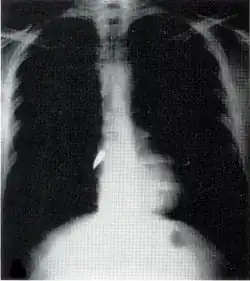

X-ray showing a bullet (white spot) in the heart

Most penetrating injuries are chest wounds and have a mortality rate (death rate) of under 10%.[14] Penetrating chest trauma can injure vital organs such as the heart and lungs and can interfere with breathing and circulation. Lung injuries that can be caused by penetrating trauma include pulmonary laceration (a cut or tear) pulmonary contusion (a bruise), hemothorax (an accumulation of blood in the chest cavity outside of the lung), pneumothorax (an accumulation of air in the chest cavity) and hemopneumothorax (accumulation of both blood and air). Sucking chest wounds and tension pneumothorax may result.